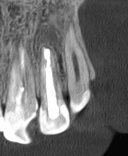

Six months later, the fistula resolved and the bone regenerated. The tooth was saved and is functioning normally.

For more than a year, the patient had a persistent fistula near the upper lateral incisor. The tooth had already been retreated through the root canal at another clinic, but the inflammation kept returning. An infection remained at the root tip, and extraction was becoming a real possibility.